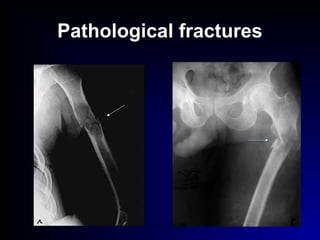

Pathological fractures

 Pathological fr.:

- general causes : senile osteoporosis

endocrinal diseases:

( hyperparathyroidism, Cushing syndrome)

- local causes : inflammation

tumor

bone cyst, fibrous lesion